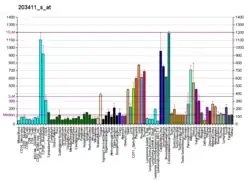

Mutations in the LMNA gene are associated with several diseases, including Emery–Dreifuss muscular dystrophy, familial partial lipodystrophy, limb girdle muscular dystrophy, dilated cardiomyopathy, Charcot–Marie–Tooth disease, and restrictive dermopathy. A truncated version of lamin A, commonly known as progerin, causes Hutchinson-Gilford-Progeria syndrome.[12][13] To date over 1,400 SNPs are known [1]. They can manifest in changes on mRNA, splicing or protein (e.g. Arg471Cys,[14] Arg482Gln,[15] Arg527Leu,[11] Arg527Cys,[16] Ala529Val [17] ) level.